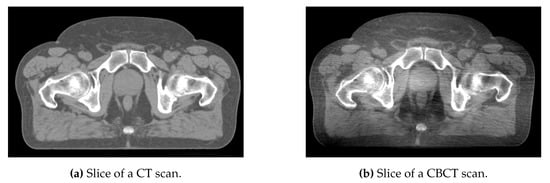

CT and CBCT are both based on X-ray propagation through the patient’s body. However, the CBCT scans are of lower quality than CT scans due to different types of artifacts, including noise, beam hardening, and scattering, as shown in Figure 1. In particular, scattering is an important limitation that could rule out the use of CBCT for radiotherapy treatment planning []. However, CBCT scans are currently used in order to detect daily variations in patient anatomy, which are particularly large in the pelvic region due to physiological function (e.g., bladder and rectal filling and voiding). Detecting such variations is important since they can impair treatment dose conformity, which means delivering too large a dose to the healthy organs (e.g., the bladder and rectum in the case of prostate cancer) and too low a dose to the clinical target volume (which simply corresponds to prostate itself for a significant proportion of patients) []. To improve treatment dose conformity in the pelvic region further, proposals have been made to change treatment plan delivery as a function of time based on observed anatomic variations [,].

Figure 1.

Comparison of CT and CBCT scans